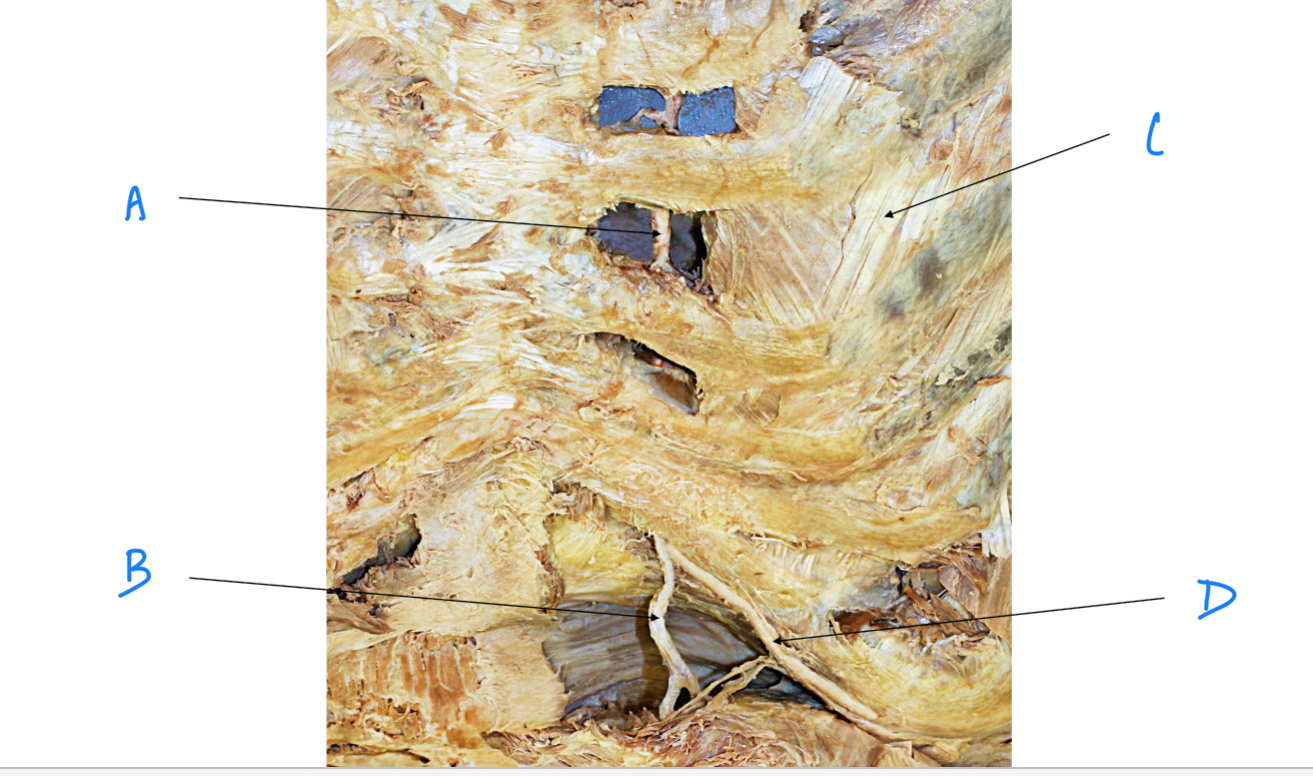

A. Identify structure

Transverse foramen; Vertebral a.

B. Identify structure; What goes through this feature?

Transverse process

C. Identify structure